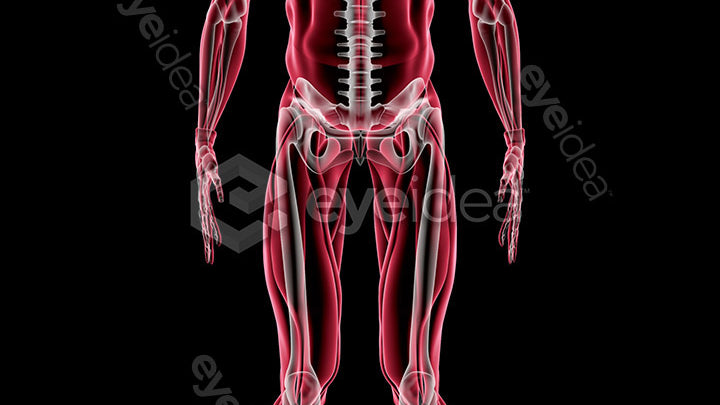

Versatility and Variety

Our Stock-Packs™ are curated to include a varied

range of angles, motion, styles and formats,

ensuring that creators can find the assets

they want fast and easy.